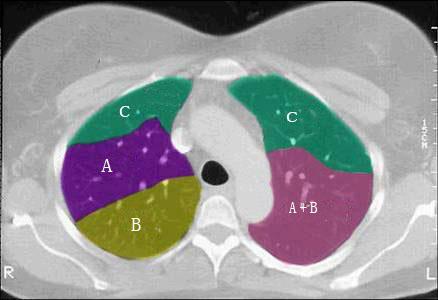

问题 结合肺段模式肺动脉干与右肺动脉层面、心室层面、主动脉弓层面、左右心房层面图(如图),选出左肺下叶的组成 ( )

选项 A.G+H+I+J B.F +H+I+J C.E+F+G+H+I+J D.D+E+F+G+H+I+J E.C+D+E+F+G+H+I+J

答案 B